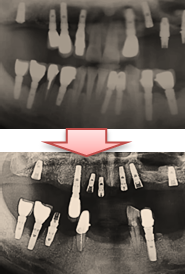

◈ 심각한 잇몸의 골 소실에도 다시 임플란트가 가능할까?

의사마다 차이는 있지만 골 소실이 심하면 다수의 뼈 이식을 한 후 임플란트를 하는 경우도 있다.

뼈 이식은 한 번에 되는 것이 아니고 여러 번 시술하기 때문에 시간이 많이 걸린다.

모든 임플란트를 제거한 후 다시 임플란트를 하는 과정은 그리 만만치가 않다.

뼈 이식한 후 단계적으로 진행해야 하기 때문이다.

모든 치아를 임플란트로 하는데 보통 1년 반이라는 시간이 걸린다.